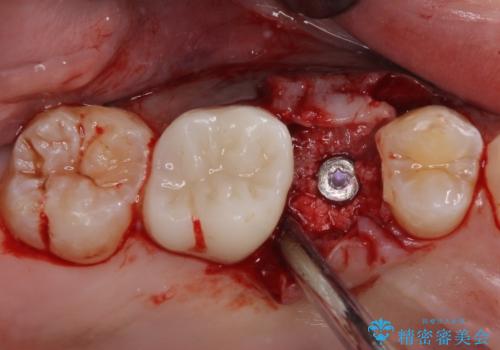

患者様自身も何となく違和感を覚えていたとのことで、インプラント補綴治療を行うこととしました。

歯列不正は比較的軽微であったので、インビザラインによる矯正治療とし、矯正治療中にタイミングを見て抜歯とインプラント埋入を行う予定としました。

破折して抜歯が必要となった歯の後ろの歯は、根管治療が必要な状態であったので、根管治療を行い、矯正治療後にインプラント部の補綴治療と同時にセラミッククラウンを装着しました。